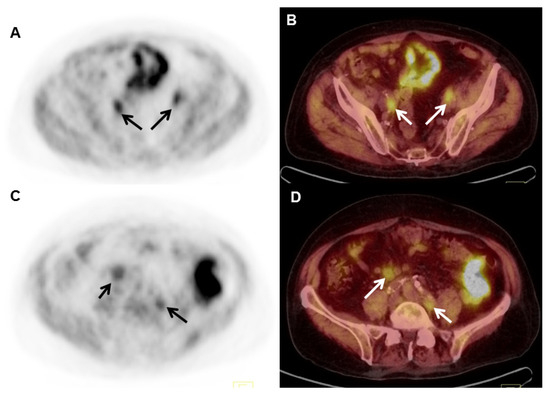

- Calais, J.; Ceci, F.; Eiber, M.; Hope, T.A.; Hofman, M.S.; Rischpler, C.; Bach-Gansmo, T.; Nanni, C.; Savir-Baruch, B.; Elashoff, D.; et al. 18F-fluciclovine PET-CT and 68Ga-PSMA-11 PET-CT in patients with early biochemical recurrence after prostatectomy: A prospective, single-centre, single-arm, comparative imaging trial. Lancet Oncol. 2019, 20, 1286–1294. [Google Scholar] [CrossRef]